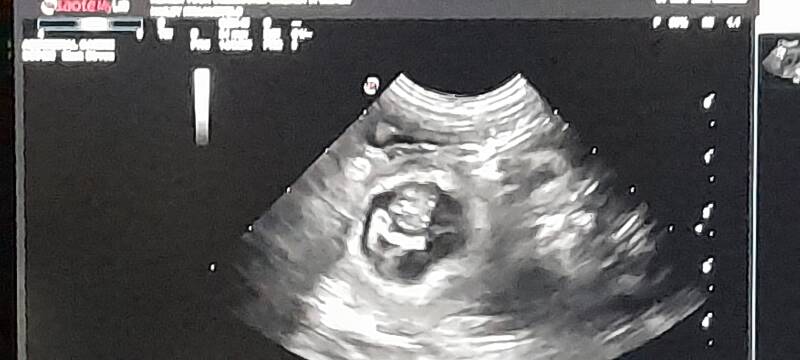

January 4, 2022.

Hopefully the year will start well and Hailey will be pregnant.

Really exciting, because in the weeks before you see things that you think she is pregnant, but it is always nice to have it confirmed.

We had the ultrasound early, so we quickly knew if she was pregnant,

When contact was made with the ultrasound machine you saw very quickly that she is pregnant. So nice to see that.

Awesome!!!! Hailey is going to be a mother!! We are so happy with it.

I am so looking forward to this litter.